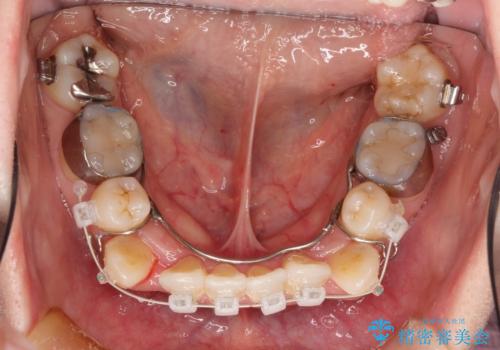

- 審美装置(ブラケット:白/ワイヤー:白)

スペースの不足量が著しく、上下左右の抜歯を伴うワイヤー矯正にて治療を行いました。

抜歯によるスペースを利用し、強いがたつきの改善を行いました。

また、左上の奥歯に関して親知らずの1つ手前の歯の状態が悪かったため、その歯は抜歯をし親知らずを利用して噛み合わせを作りました。

治療に関して期間こそかかってしまったものの、見た目、嚙み合わせ及び、治療期間や施術内容に大変ご満足いただきました。